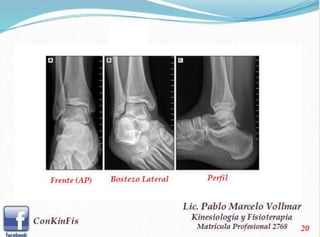

El esguince de tobillo es una lesión que compromete a los ligamentos de la articulación del tobillo, ya sean del lado externo o interno. Produce un daño que puede ir desde una simple distensión hasta la rotura completa. Existen varios grados de esguince, los que van a depender de la indemnidad del ligamento. Los Tipo I corresponden a una distensión, sin rotura de fibras ligamentosas. El esguince Tipo II corresponde a roturas parciales del ligamento y el Tipo III son roturas completas del ligamento. Hoy en día se realiza un tratamiento funcional, es decir, una inmovilización con algún tipo de tobillera especial o bota que le permita al paciente realizar rehabilitación en forma paralela a la medida de inmovilización. De esta manera disminuye menos la masa muscular, no pierde tanto rango articular, mejora su respuesta al dolor y disminuye más rápido la inflamación. El tratamiento va a depender del tipo de esguince que sea. En los grado I ó II, con mínimo compromiso ligamentoso, se usan métodos de inmovilización parcial con órtesis que son semirígidas. Esto le permite a la persona conservar la movilidad en extensión y en flexión, y por lo tanto va a caminar sin la posibilidad de torcerse el tobillo. Si el paciente tiene demasiado dolor, es preferible usar en los primeros días una bota inmovilizadora, la cual permite que disminuya la inflamación y dolor para que cuando esté en condiciones de poder realizar una flexoextensión de tobillo en mejores condiciones, se pasa a cualquiera de las órtesis semirígidas. De esta manera puede seguir su rehabilitación y en el plazo de tres a cuatro semanas estará en condiciones de iniciar alguna actividad deportiva multidireccional. Normalmente las lesiones menores, como esguinces grado I ó II van a demorar alrededor del mes en volver a una actividad física competitiva y los grado III sobre los dos meses de evolución, siempre y cuando estén tratados correctamente.